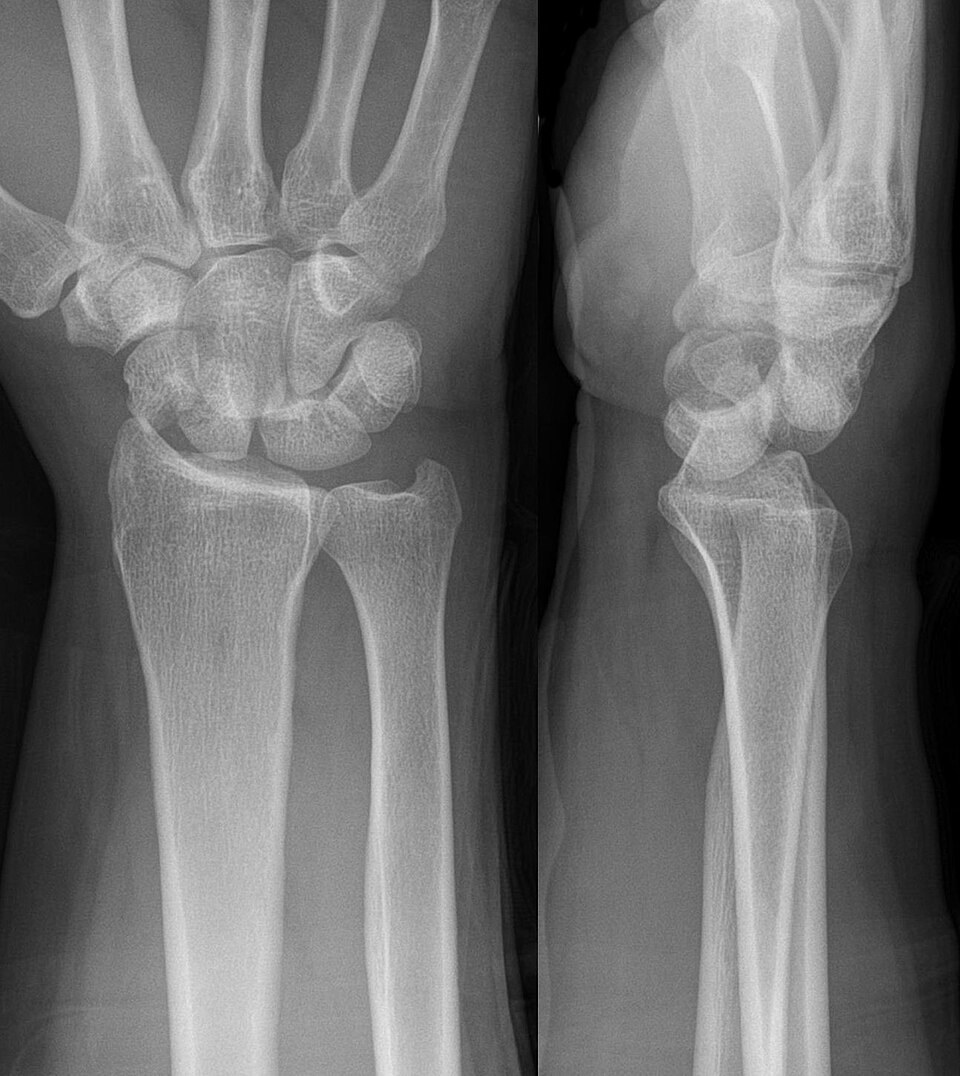

Because of the high energy associated with these injuries, perilunate dislocations, lunate dislocations, and perilunate fracture-dislocations account for less than 10% of all wrist injuries.25 High force applied to a hyperextended wrist in situations such as falls from heights on an outstretched hand or motor vehicle collisions can destabilize the surrounding structure through fractures and disruptions in articulations or ligaments, which may cause a perilunate dislocation, lunate dislocation, and/or perilunate fracture-dislocation. (See Figure 4.) The mechanism typically is wrist hyperextension, ulnar deviation, and intercarpal supination. In the case of perilunate dislocation, the lunate maintains its articulated position with the distal radius while the surrounding carpal bones dislocate dorsally. The most common symptoms are pain, swelling, and deformity. Loss of grip strength can occur, as well as median nerve compression, leading to paresthesia or numbness in the median distribution.26,27 This typically is present with more instability than lunate dislocations because of the involvement of multiple carpal bones.

Figure 4. Perilunate Fracture Dislocation |

![]() |

Source: Hellerhoff. https://commons.wikimedia.org/wiki/File:Transscaphoid_perilunate_fracture-dislocation_-_39jm_-_Roe_ap_und_seitlich_-_001.jpg |

The Mayfield classification divides perilunate instability into four stages. In stage one, there is rotatory subluxation of the scaphoid, disrupting the scapholunate ligament. On AP X-ray, increased distance indicates scapholunate dissociation for more than 3 mm can be seen, known as the Terry-Thomas sign. Stage two involves the lunocapitate disruption, and the lunate can project through the space of Poirier, which is an area between the capitate and lunate that has poor ligamentous support. In this stage, the lunate remains within normal alignment with the distal radius, where the remaining carpal bones are dislocated. Scaphoid fractures are common and typically are present in up to 60% of cases of lunocapitate disruption. In stage three, the lunotriquetral interosseous ligament is disrupted. Triquetral fracture also can be seen with this stage of injury. In this stage, neither the lunate nor capitate is aligned with the distal radius. The lunate is dislocated in stage four, involving the dorsal radiolunate ligament. A tipped teacup appearance can be seen on X-ray. (See Figure 5.) Physicians can attempt closed reduction, but it often is unsuccessful because of the complexity.26,27 Open reduction and internal fixation (ORIF) is the gold standard in treatment for this type of injury and allows for repair of ligamentous and bony injuries.26,27

Figure 5. Lunate Dislocation with Spilled Teacup Sign |

Source: James Heilman, MD. https://commons.wikimedia.org/wiki/File:LunatedislocationL.jpg |

Perilunate dislocations typically are caused by high-energy traumas, such as falls from heights or motor vehicle collisions. The mechanisms typically involve wrist hyperextension, ulnar deviation, and intercarpal supination. The force vector travels from radial to ulnar direction, causing instability and damage to the complex ligamentous structures of the wrist. The most common symptoms are pain, swelling, and deformity. Loss of grip strength can occur, as well as median nerve compression, leading to paresthesia or numbness in the median distribution.26,27 Perilunate dislocations typically present with more instability than lunate dislocations because of the involvement of multiple carpal bones. Hand radiography usually is sufficient for diagnosis; however, CT scanning can be useful in assessing the extent and surgical planning.27